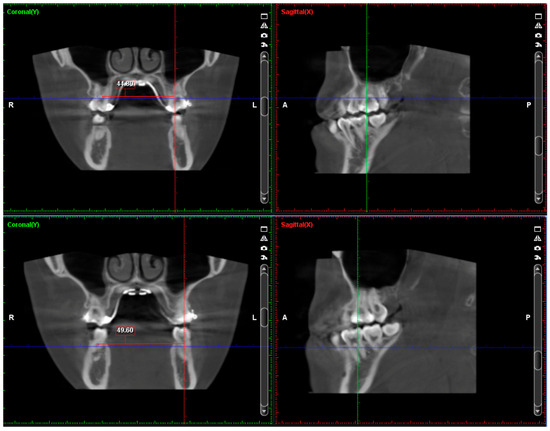

2.4. Treatment Progress